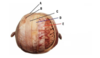

What is A?

Compact bone

What is B?

Spongy bone

What are the 3 layers of the skull bone?

Compact bone, spongy bone, compact bone

Which part of the skull bone houses red marrow?

Spongy bone